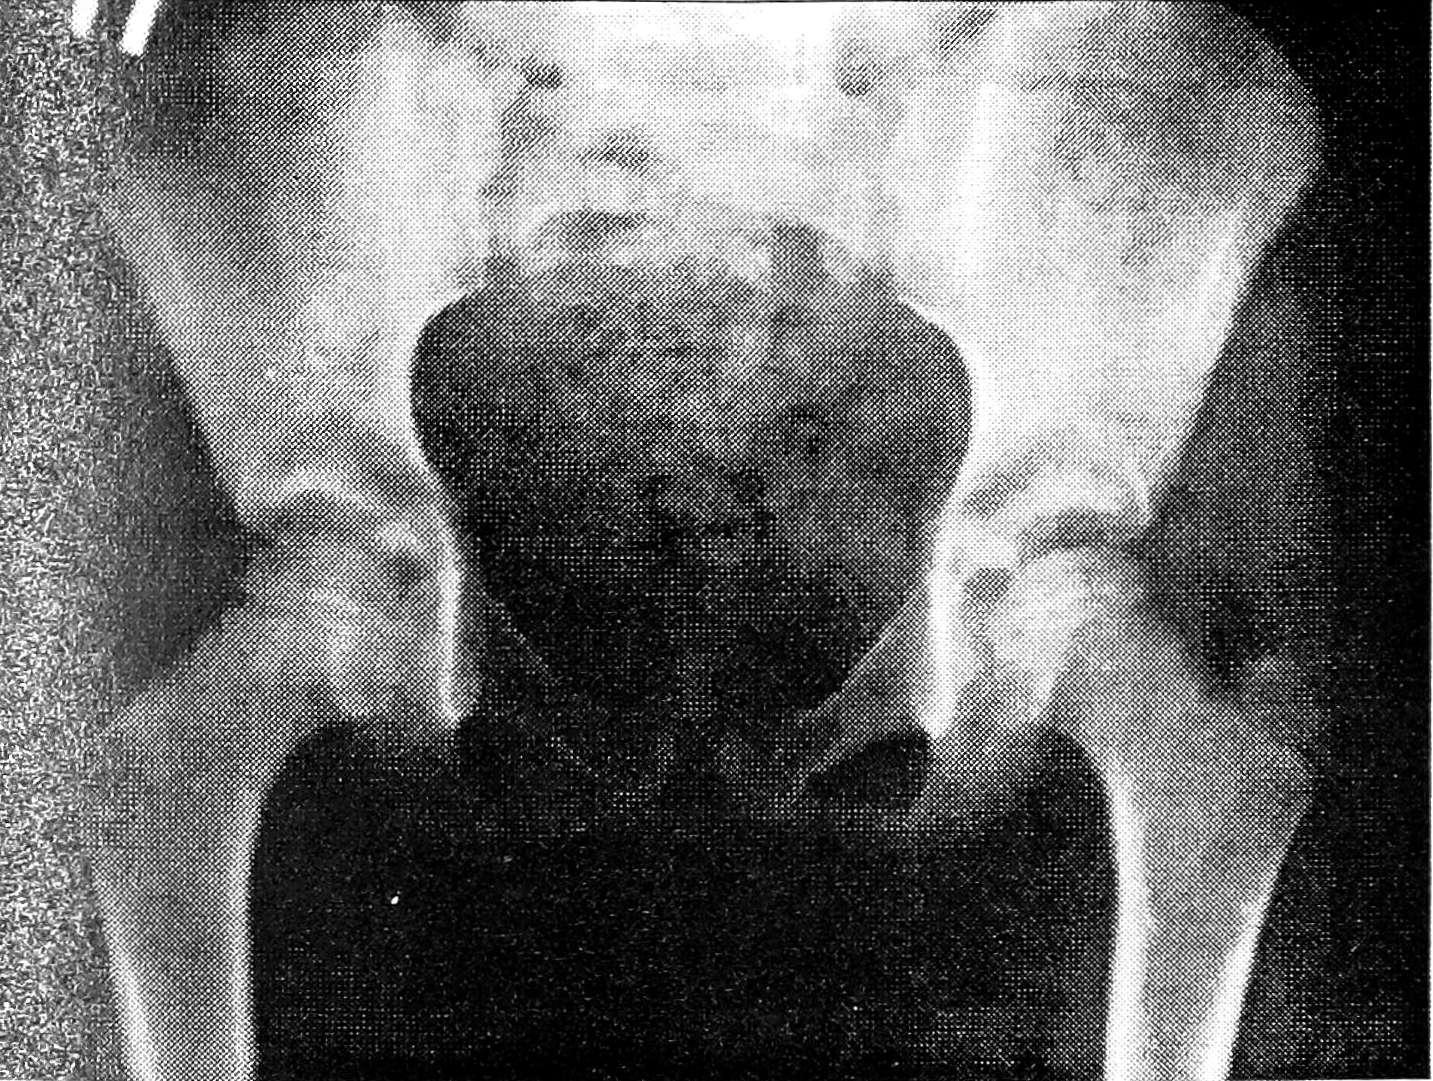

Рис. 1. Больной Т. 5 лет. Клинический диагноз: левосторонняя болезнь Пертеса.

В области «здоровой» головки правого бедра определяется неравномерное уплотнение костной структуры.

При изучении головки бедренной кости (у детей с односторонней БП особое внимание обращали на так называемый «здоровый» сустав) учитывали: наличие остеопороза или остеосклероза, уплощение, характер контуров (гладкие, неровные), структуру (от равномерной до фрагментированной). Типичная картина двустороннего асептического некроза головки бедренной кости выявлена у 11 больных. У 20 пациентов с клиническим диагнозом односторонней БП типичные признаки асептического некроза «здоровой» головки бедра с фрагментацией ее отсутствовали. У 18 из них отмечались: неравномерная структура головки — у 3, незначительное или умеренное уплощение — у 12, остеопороз — у 3, неровные контуры — у 3 (рис. 1 и 2 на вклейке). При динамическом наблюдении на протяжении 2—3 лет эти микросимптомы на «здоровой» стороне у 2 больных развились в типичную картину асептического некроза головки бедренной кости. Лишь у 2 из 20 пациентов изменения выявлялись только с одной стороны: у одного ребенка (12 лет) была типичная картина односторонней БП, у другого (5 лет) изменения ограничивались неравномерностью структуры и неровностью контуров головки бедра.